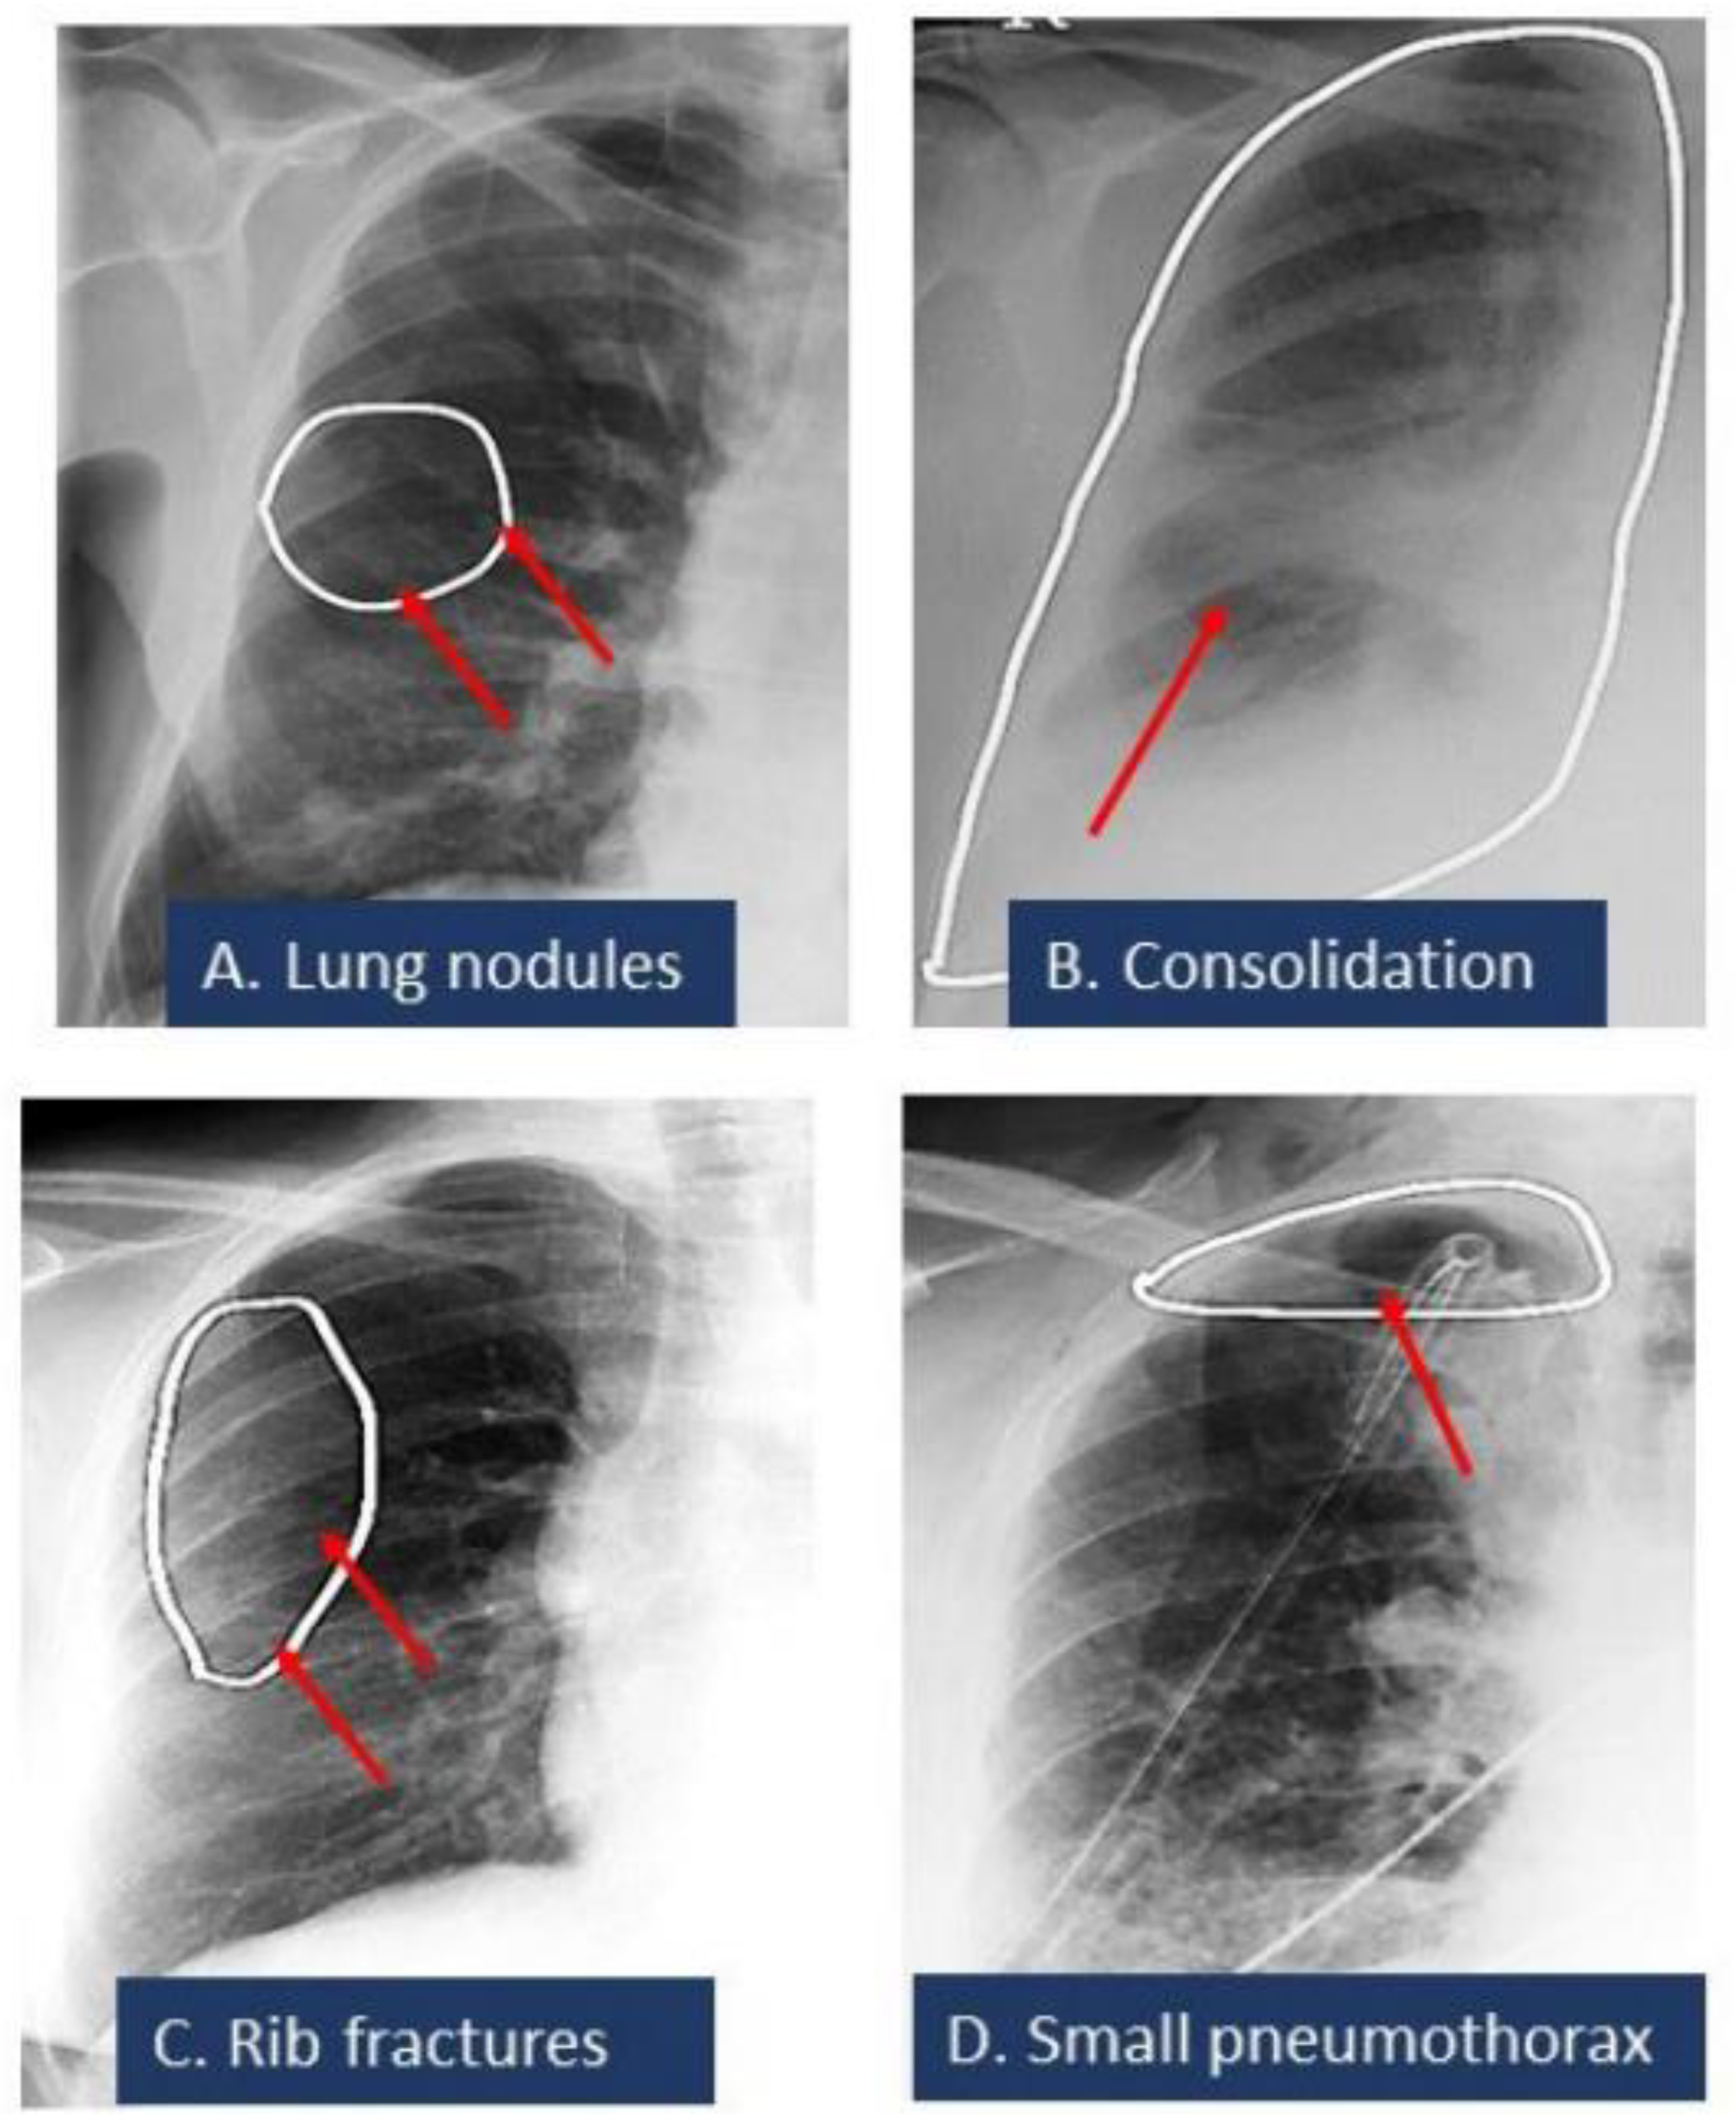

| Consolidation | 49 | 3 | 3 | 0 | 4 | 0 | 0 | 0 | 3 | 0 | 0 | 0 |

| Pulmonary nodule | 28 | 1 | 8 | 1 | 8 | 1 | 3 | 0 | 2 | 0 | 2 | 0 |

| Pneumothorax | 68 | 6 | 20 | 1 | 2 | 0 | 0 | 0 | 3 | 0 | 0 | 0 |

| Pleural effusion | 10 | 0 | 0 | 1 | 1 | 0 | 0 | 0 | 2 | 0 | 1 | 0 |

| Rib fracture | 36 | 0 | 9 | 0 | 3 | 0 | 0 | 0 | 0 | 0 | 0 | 0 |

| Pulmonary nodule | 96 | 100 | 96 | 0.98 (0.94–1.00) |

| Consolidation | 98 | 100 | 98 | 0.99 (0.97–1.00) |

| Rib fracture | 87 | 100 | 94 | 0.94 (0.85–1.00) |

| Pleural effusion | 100 | 17 | 67 | 0.82 (0.54–1.00) |

| Pneumothorax | 84 | 100 | 85 | 0.92 (0.86–0.98) |